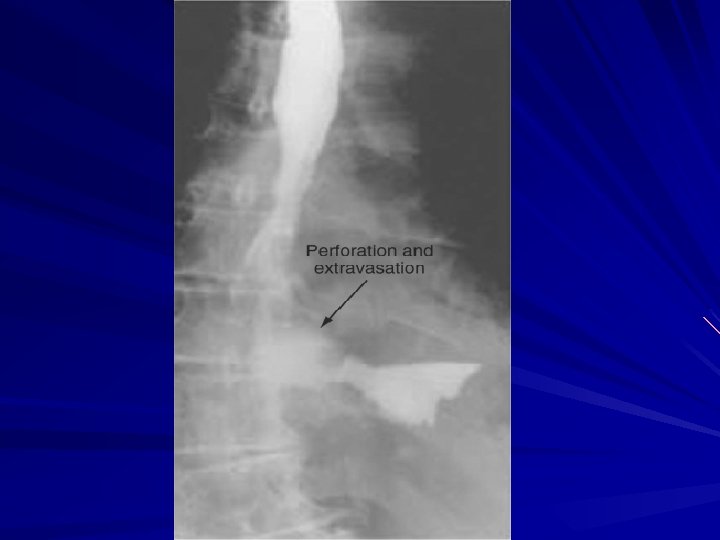

Esophageal Perforation of the esophagus is a surgical emergency Early detection and surgical repair within the first 24 hours results in 80% to 90% survival after 24 hours, survival decreases to less than 50%

Esophageal Perforation from forceful vomiting (Boerhaave's syndrome), foreign body ingestion, or trauma accounts for 15%, 14%, and 10% of cases, respectively Most esophageal perforations occur after endoscopic instrumentation for a diagnostic or therapeutic procedure,

Symptoms and Diagnosis of an esophageal perforation may be made radiographically A chest roentgenogram may demonstrate a hydropneumothorax A contrast esophagram is done using barium for a suspected thoracic perforation and Gastrografin for an abdominal perforation.

Symptoms and Diagnosis Most perforations are found above the GEJ on the left lateral wall of the esophagus which results in a 10% false -negative rate in the contrast esophagram if the patient is not placed in the lateral decubitus position Chest CT shows mediastinal air and fluid at the site of perforation